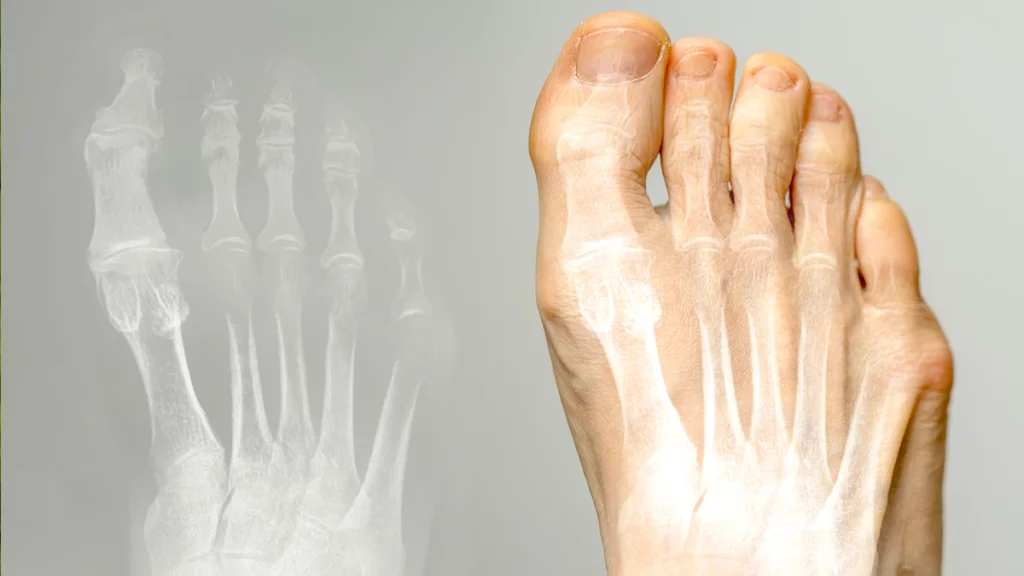

Traditional open bunion corrections require long incisions and significant dissection, leading to increased pain, swelling and scarring, and prolonged recovery time compared to minimally invasive techniques. Minimally invasive bunion surgery involves minimal incisions with improved precision of the correction, resulting in significantly less pain and swelling postoperatively, reduced scarring, and faster return to normal activities.

Minimally invasive bunion correction offers improved cosmetic outcomes due to the use of smaller incisions, resulting in less noticeable scarring. This approach allows for more precise surgical techniques, enhancing both the function and appearance of the foot post-surgery.

Minimally invasive bunion surgery offers improved outcomes by allowing for more precise correction with smaller incisions, which leads to less tissue damage and a quicker recovery. Patients experience reduced pain, swelling, and scarring compared to traditional open surgery, resulting in both functional and cosmetic benefits. The enhanced precision of the procedure also contributes to a lower risk of complications, such as infection or recurrence of the bunion. Overall, this approach provides a faster return to normal activities with long-lasting, more satisfying results for patients.